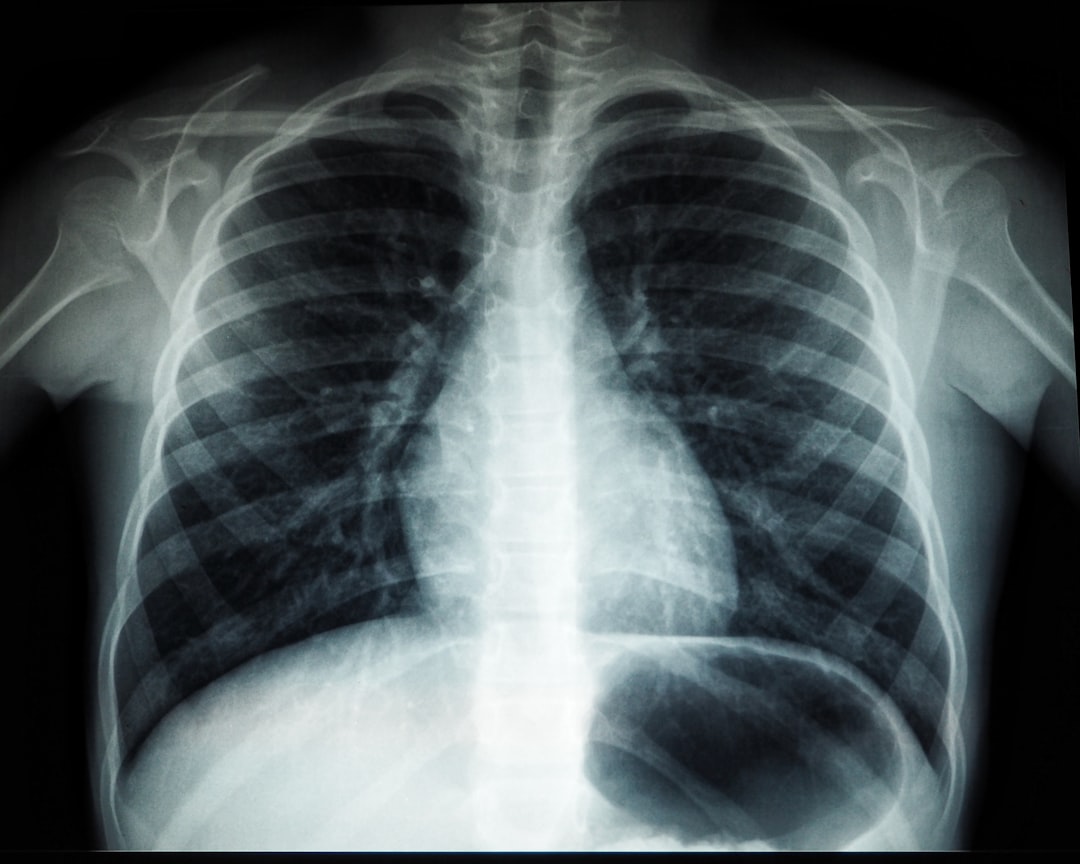

잠복결핵은 많은 사람들에게 심각한 건강 문제를 일으킬 수 있습니다. 본문에서는 잠복결핵 검사 종류, 비용, 치료법에 대해 자세히 알아보겠습니다.

잠복결핵 검사 종류

잠복결핵 검사는 크게 두 가지 유형으로 나뉩니다. 첫 번째는 투베르쿨린 피부 검사(TST)이며, 두 번째는 혈액 검사(IGRA)입니다. TST는 예전부터 널리 시행되어온 검사 방법으로, 피부에 결핵 단백질을 주입한 후 48시간에서 72시간 이내에 결과를 확인합니다. 이 검사 방법은 간단하고 비용이 저렴하다는 장점이 있지만, 잠복결핵 양성 결과가 나오는 경우에도 이를 실제 감염자로 오해할 가능성이 있습니다.

다음으로 IGRA는 혈액 검사를 통해 결핵 감염의 유무를 검토합니다. 이 검사는 주로 TST 결과가 애매할 때 사용되며, 결핵 감염 여부를 더 정확하게 판단할 수 있습니다. 여러 연구에 따르면, IGRA는 잠복결핵 검사 유효기간이 길고, 재검사를 통해 정확도가 높은 결과를 제공합니다. 이러한 검사 방법을 통해 우리는 잠복결핵 감염 여부를 보다 확실히 알 수 있습니다.